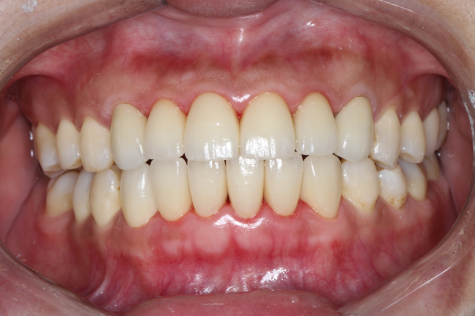

全瓷修复后的牙齿

不到一个小时,牙龈上的黑线消失了,牙齿又恢复了往日的风采,董女士开心的笑了,她说道:“以后又可以开心的和客户交谈了,感谢熊医生,感谢麦芽口腔先进的技术,以后一定好好的护理自己的牙齿!”